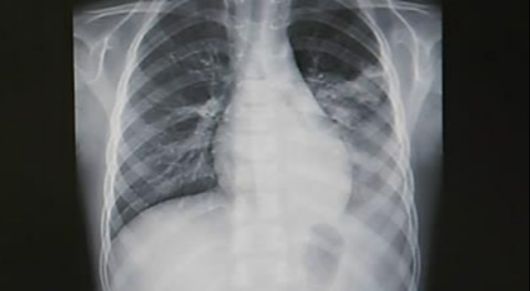

폐렴은 주로 세균성 또는 바이러스성 감염에 의해 유발되는 폐의 염증성 질환으로 대부분 2~4주 내에 호전된다. 그러나 영아, 고령자, 심장 또는 폐 질환 환자 등 취약 집단은 중증으로 진행될 위험이 높다.

폐렴의 주요 증상으로는 노란색 또는 녹색 점액(가래)을 동반할 수 있는 지속적인 기침, 숨 가쁨 및 흉통, 쌕쌕거리는 숨소리, 고열, 몸살, 극심한 피로감, 일시적인 식욕 부진 등이 대표적이다.

한편 세계보건기구(WHO)는 2~11개월 영아의 분당 호흡수 50회 이상, 1~5세의 40회 이상을 폐렴 가능성으로 본다. 여기에 갈비뼈 아래가 안쪽으로 들어가는 흉벽 함몰, 숨 쉴 때 끙끙거리거나 비정상적인 호흡음, 젖·물·식사 거부, 축 처진 의식 상태, 청색증 등이 동반되면 즉시 응급평가가 필요하다.

그러나 영아 폐렴은 이런 전형적 징후 없이도 진행될 수 있다. 단순 감기처럼 보이는 열, 반복 구토, 평소보다 심한 피로감, 잠만 자려는 행동, 혹은 부모가 가슴에서 느끼는 이상한 숨소리 같은 비특이적 변화가 초기 신호일 수 있다.

실제로 국내외 연구에서도 소아 폐렴은 열·기침·호흡 곤란이 모두 나타나는 전형적 패턴보다, 비특이적 증상들의 조합으로 시작되는 경우가 더 흔한 것으로 보고되고 있다.